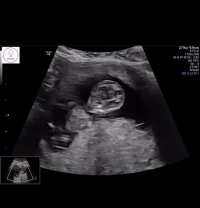

Syns dette ser veldig ut som en gutt, pga det «laget» oppå + at den går oppover. Men har du noen flere bilder?13+2 noen som har en tanke her? Synst selv nubben her er mye flatere enn med gutten jeg har

Har disse, men tror ikke nub viser herSyns dette ser veldig ut som en gutt, pga det «laget» oppå + at den går oppover. Men har du noen flere bilder?![]()

Siste bilde så kan se se ut som en guttHar disse, men tror ikke nub viser her